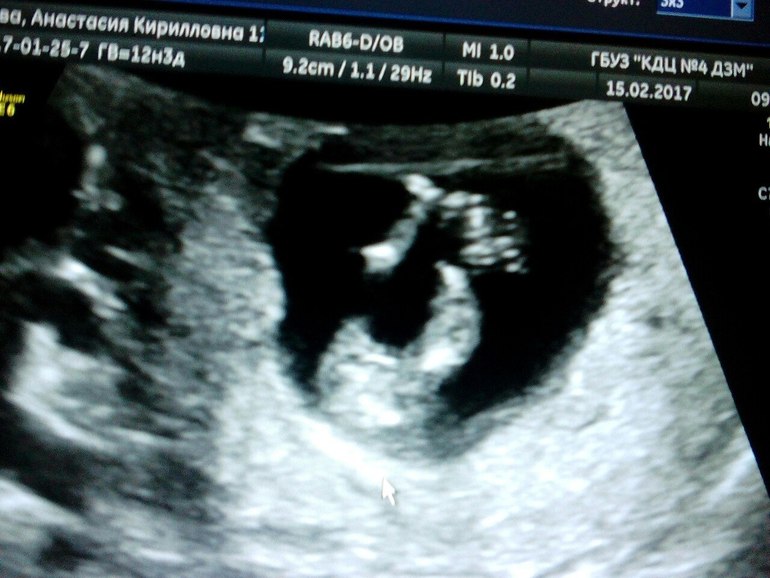

как сказала врач?мальчика не вижу))) скорее всего девочка!!!! У нас все хорошо, но надо дождаться анализов крови!!!

Сходили в ЖК, всё у нас хорошо,анализы,как сказали показательные. Живот наш ждать нам явно недели до 20, ну это как всегда. На 15 февраля назначили скрининг. Ждемс, может скажут кто живет у нас тама

. С ребятами всегда говорили на 12-13 неделе. А сегодня приснилось, пришли на УЗИ, врач спрашивает,вы как называть хотели, ну говорю, девочку Ева мальчика Андрей, а она......ну что же... Привет Андрей)))))))